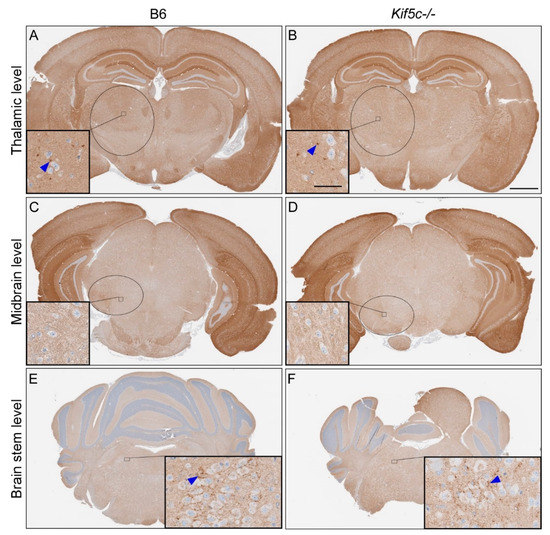

3.1. The 22 L PrPSc Spreading Kinetics in B6 and Kif5c−/− Mice

3.2. Stereotactic Kinetics of ME7 Scrapie at 40 Days Post-Inoculation (dpi)